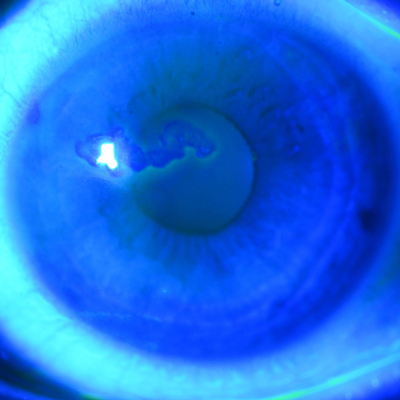

Stephanie Chen, MD, dove into the cost and waste reduction achieved from transitioning to a reusable phaco platform and reusable diamond knives, from her recent study published in JCRS. Dr. Chen also discussed the multisociety position paper published in JCRS advocating for access to multiuse phaco cassettes.